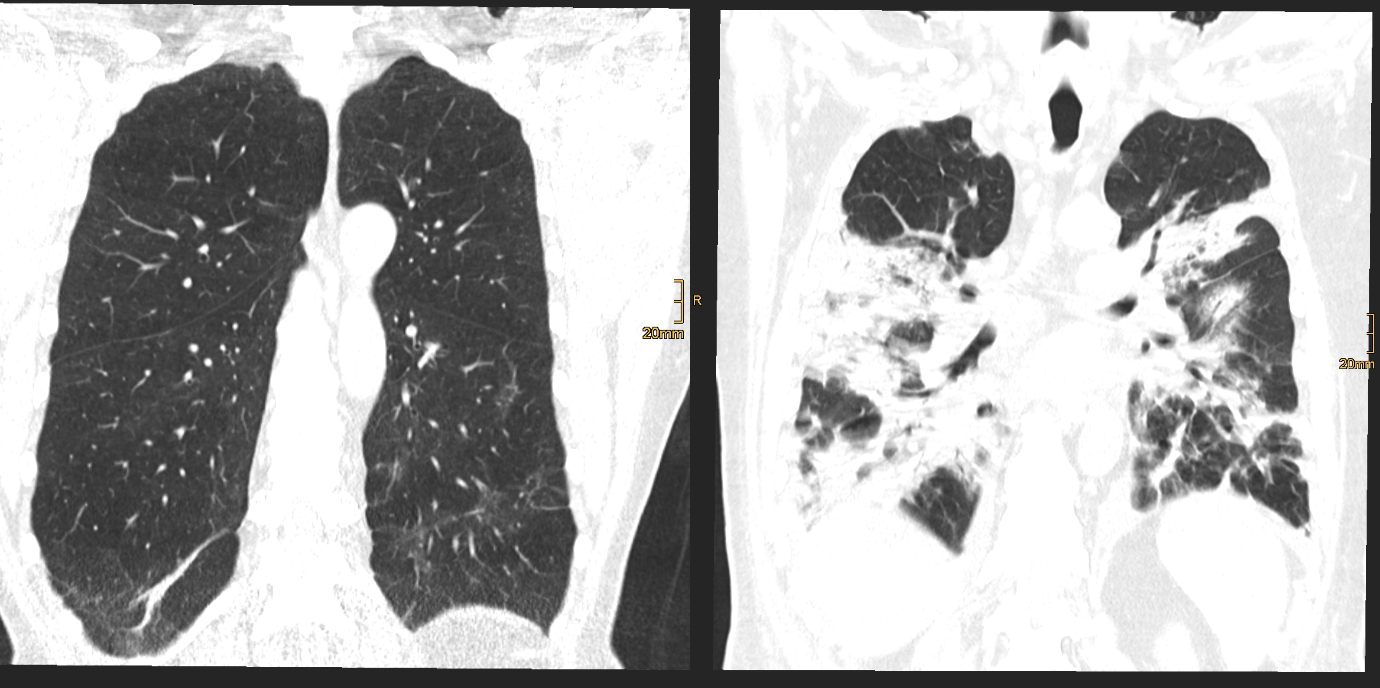

Eine aktuelle, kürzlich im angesehenen Fachjournal Radiology veröffentlichte Ein-Jahres-Folgestudie des Teams um den Radiologen Gerlig Widmann liefert nun neue Erkenntnisse zum Verlauf von Lungenveränderungen in der Computertomographie (CT) nach COVID-19. „In unserer viergeteilten Kohorte* betreffend den Schweregrad des initialen Verlaufes waren bei mehr als der Hälfte der TeilnehmerInnen auch noch zwölf Monate nach Krankenhausentlassung subtile Veränderungen im CT nachweisbar. Auch wenn eine Mehrheit dieses Anteils zumindest schwer erkrankt war, sind wir von diesem Ergebnis doch ein wenig überrascht. Der über 60-jährige männliche Patient mit kritischem Krankheitsverlauf trägt unseren Untersuchungen zufolge jedenfalls das größte Risiko, auch ein Jahr nach Covid-19 noch Lungenveränderungen im CT zu zeigen“, erklärt Radiologin und Erstautorin Anna Luger. Insgesamt wurden vier CT-Verlaufskontrollen der Lunge durchgeführt, von anfangs 142 ProbandInnen konnten nach einem Jahr noch 91 TeilnehmerInnen in die Studie eingeschlossen werden.

Im Detail zeigten 34 Prozent der TeilnehmerInnen oberflächennahe netzartige Verdichtungen der Lunge, geringe Milchglastrübungen oder beides, bei 20 Prozent der TeilnehmerInnen waren ausgedehnte Milchglastrübungen, oberflächennahe netzartige Verdichtungen, Bronchialerweiterungen und mikrozystische Veränderungen feststellbar, die eventuell auf Vernarbungsprozesse hindeuten. „Aus radiologischer Sicht lässt sich noch nicht abschätzen, wie sich diese strukturellen Lungenveränderungen zeitlich weiter verhalten“, so der Leiter der Radiologie in der interdisziplinären Studiengruppe, Gerlig Widmann. Drei Szenarien seien jedoch vorstellbar: Die Veränderungen bilden sich langsam vollständig zurück, die Veränderungen halten an und es entwickeln sich stabile Vernarbungen, oder das Lungengewebe wird zunehmend fibrotisch (Bindegewebsvermehrung) und es kommt begleitend zu kontinuierlich zunehmenden klinischen Symptomen. „In jedem Fall“, so Widmann, „werden wir den Verlauf gemeinsam mit unseren klinischen Partnern weiter wissenschaftlich begleiten“.